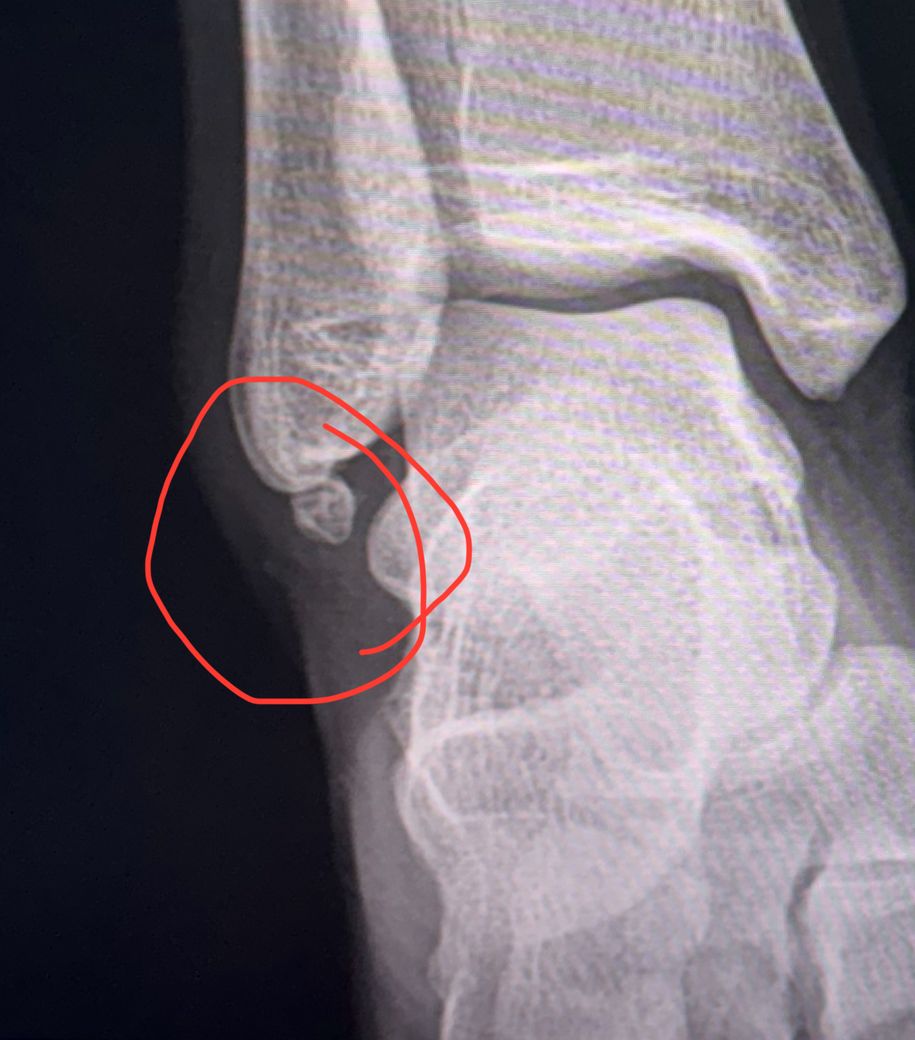

이건 뿌러진건가요 ? 냅둬도될까요 ?

최근에 계단에서 굴러 발목이 부었습니다(복숭아뼈 부분)

근데 엑스레이상 저렇게 되어있는데

예전 어릴때 뿌러진건지 지금 발목 넘어지면서 생긴건지 확답을 못받았습니다

저렇게 되어있다면 나중에 언젠가 자연스럽게 붙을까요 아님 그대로 둬도 상관없을까요 아님 수술로 제거해야될까요 ㅠ

• 생긴 모양을 볼 때에 급성으로 골절이 생긴 부분으로 보이지 않습니다. 그렇기 때문에 최근에 계단에서 굴러 발목이 다친 것과는 무관한 소견입니다.

일단은 끝부분이 떨어져 나간 (tip fracture) 것으로 보이는데요

1. 어릴 때 그랬던 것이 아직도 이 모습이다 ?

- 붙지 않으니까 제거 하는게 더 낫겠습니다

2. 지금 부러진거다?

- 부러진 정도와 양상을 종합적으로 판단해야 되겠지만

일반적으로 수술을 해서 쇠로 된 핀을 박고 깁스를 합니다

상황에 따라서는 제거를 하기도 합니다

골절은 아닐 가능성이 높습니다

부골이라고 어릴떄부터 있었을 가능성이 높습니다.